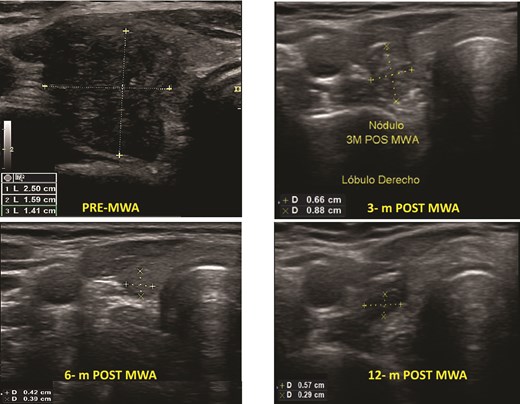

Benign thyroid nodules pre- and post-MWA (3, 6, and 12 months), see the changes in volume and the ultrasound aspect of the nodule.

Before MWA, the overall median volume was 1.54 (0.20–34.08) ml. After ablation, the 1-month, 3-month, 6-month, and 12-month median volumes were 1.80 (0.13–8.72) ml; 0.65 (0.01–12.23) ml, 0.11 (0.01–0.50) ml, and 0.05 (0.00–2.00) ml, respectively. The overall nodular volume reduced significantly after MWA treatment over time (P < .001). The VRR was 49%, 82%, 96%, and 97% at 1, 3, 6, and 12-month follow-ups, respectively (Table 3). Figure 1 shows an example of the change in volume of each patient’s nodule volume over time. The mean TSH in the 1-month follow-up was 2.84 (SD 1.61).